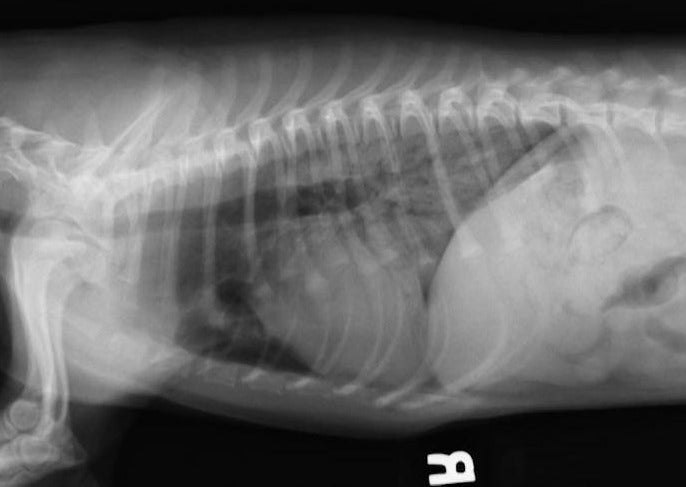

Ce séminaire sera basé sur le cas et examinera les présentations d’urgence les plus courantes pour le chien et le chat dyspnéens. Des diagnostics émergents, y compris tfAST (échographie thoracique focalisée), seront présentés, et des thérapies respiratoires seront discutées.